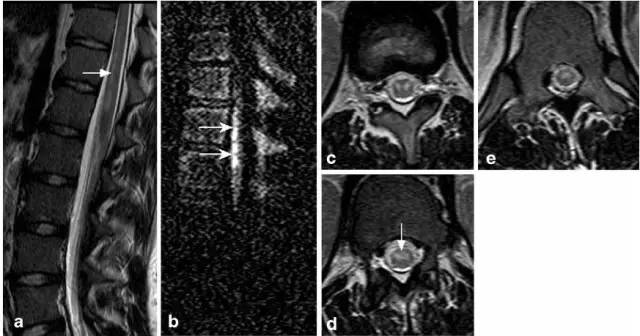

病例1:77岁女性,脊髓前动脉综合征。表现为进行性四肢瘫,剧烈颈部疼痛向双上肢放射。MRI T2(图a)显示纵向高信号,T1(图b)及强化显示脊髓腹侧轻度不均匀强化(铅笔画样;图c箭头)。T2轴位(图d,f)显示C3/4水平脊髓前角对称性高信号(图d箭头为蛇眼征;图e箭头显示轻度强化),病变扩展到C5水平,累及脊髓后动脉分布区。